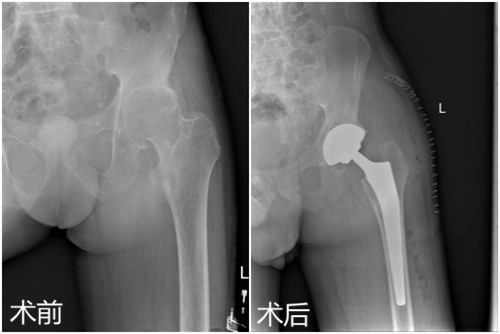

日前,临床医学院/附属医院骨三科为一名35岁强直性脊柱炎累及双侧髋关节男性患者施行了左侧人工全髋关节置换术,术后恢复良好,目前患者已经可以下地行走。该例手术的成功标志着该院骨科在复杂髋关节置换领域的技术日臻完善。

患者田先生,35岁,因身患强直性脊柱炎累及双侧髋关节,行走呈跛行步态,颈部、腰部呈僵直状,只能拄拐行走。两年前,他逐渐出现髋部疼痛不适症状,起初自行在家休息后症状稍有缓解,但两年来上述症状反复出现,并于两个月前明显加重,失去了左侧的行走能力,在当地医院就诊后效果欠佳,慕名来临床医学院/附属医院就诊。临床医学院/附属医院影像学检查显示:左髋股骨头缺血坏死继发关节退变。骨三科朱述浪主任在邀请风湿免疫科专家会诊和多次全科讨论后,决定为患者实施左侧人工全髋置换术,并制定详细的手术方案。手术过程顺利,术后切口愈合良好,术后医护人员对其进行了专业的康复锻炼,患者出院时双侧髋关节屈曲活动度超过80度。患者对临床医学院/附属医院的医疗技术及优质的护理服务予以高度赞扬。

据朱主任介绍,强直性脊柱炎是一种慢性进行性炎性疾病,因初始症状较轻,多被患者所忽略,且早期易于类风湿关节炎混淆,待发展为晚期时大关节可发生畸形和强直,病人多丧失行走能力,形同瘫痪,生活难以自理,给患者及家属带来灾难性的结果。朱主任建议,目前人工髋关节的材料与人体相容性好,设计符合生物力学,可以用30—40年,适合活动较多的年轻人,这类患者应尽早考虑髋关节置换手术治疗,其间生活能恢复自理,生活质量提高,能够大大减轻患者及家庭的负担。